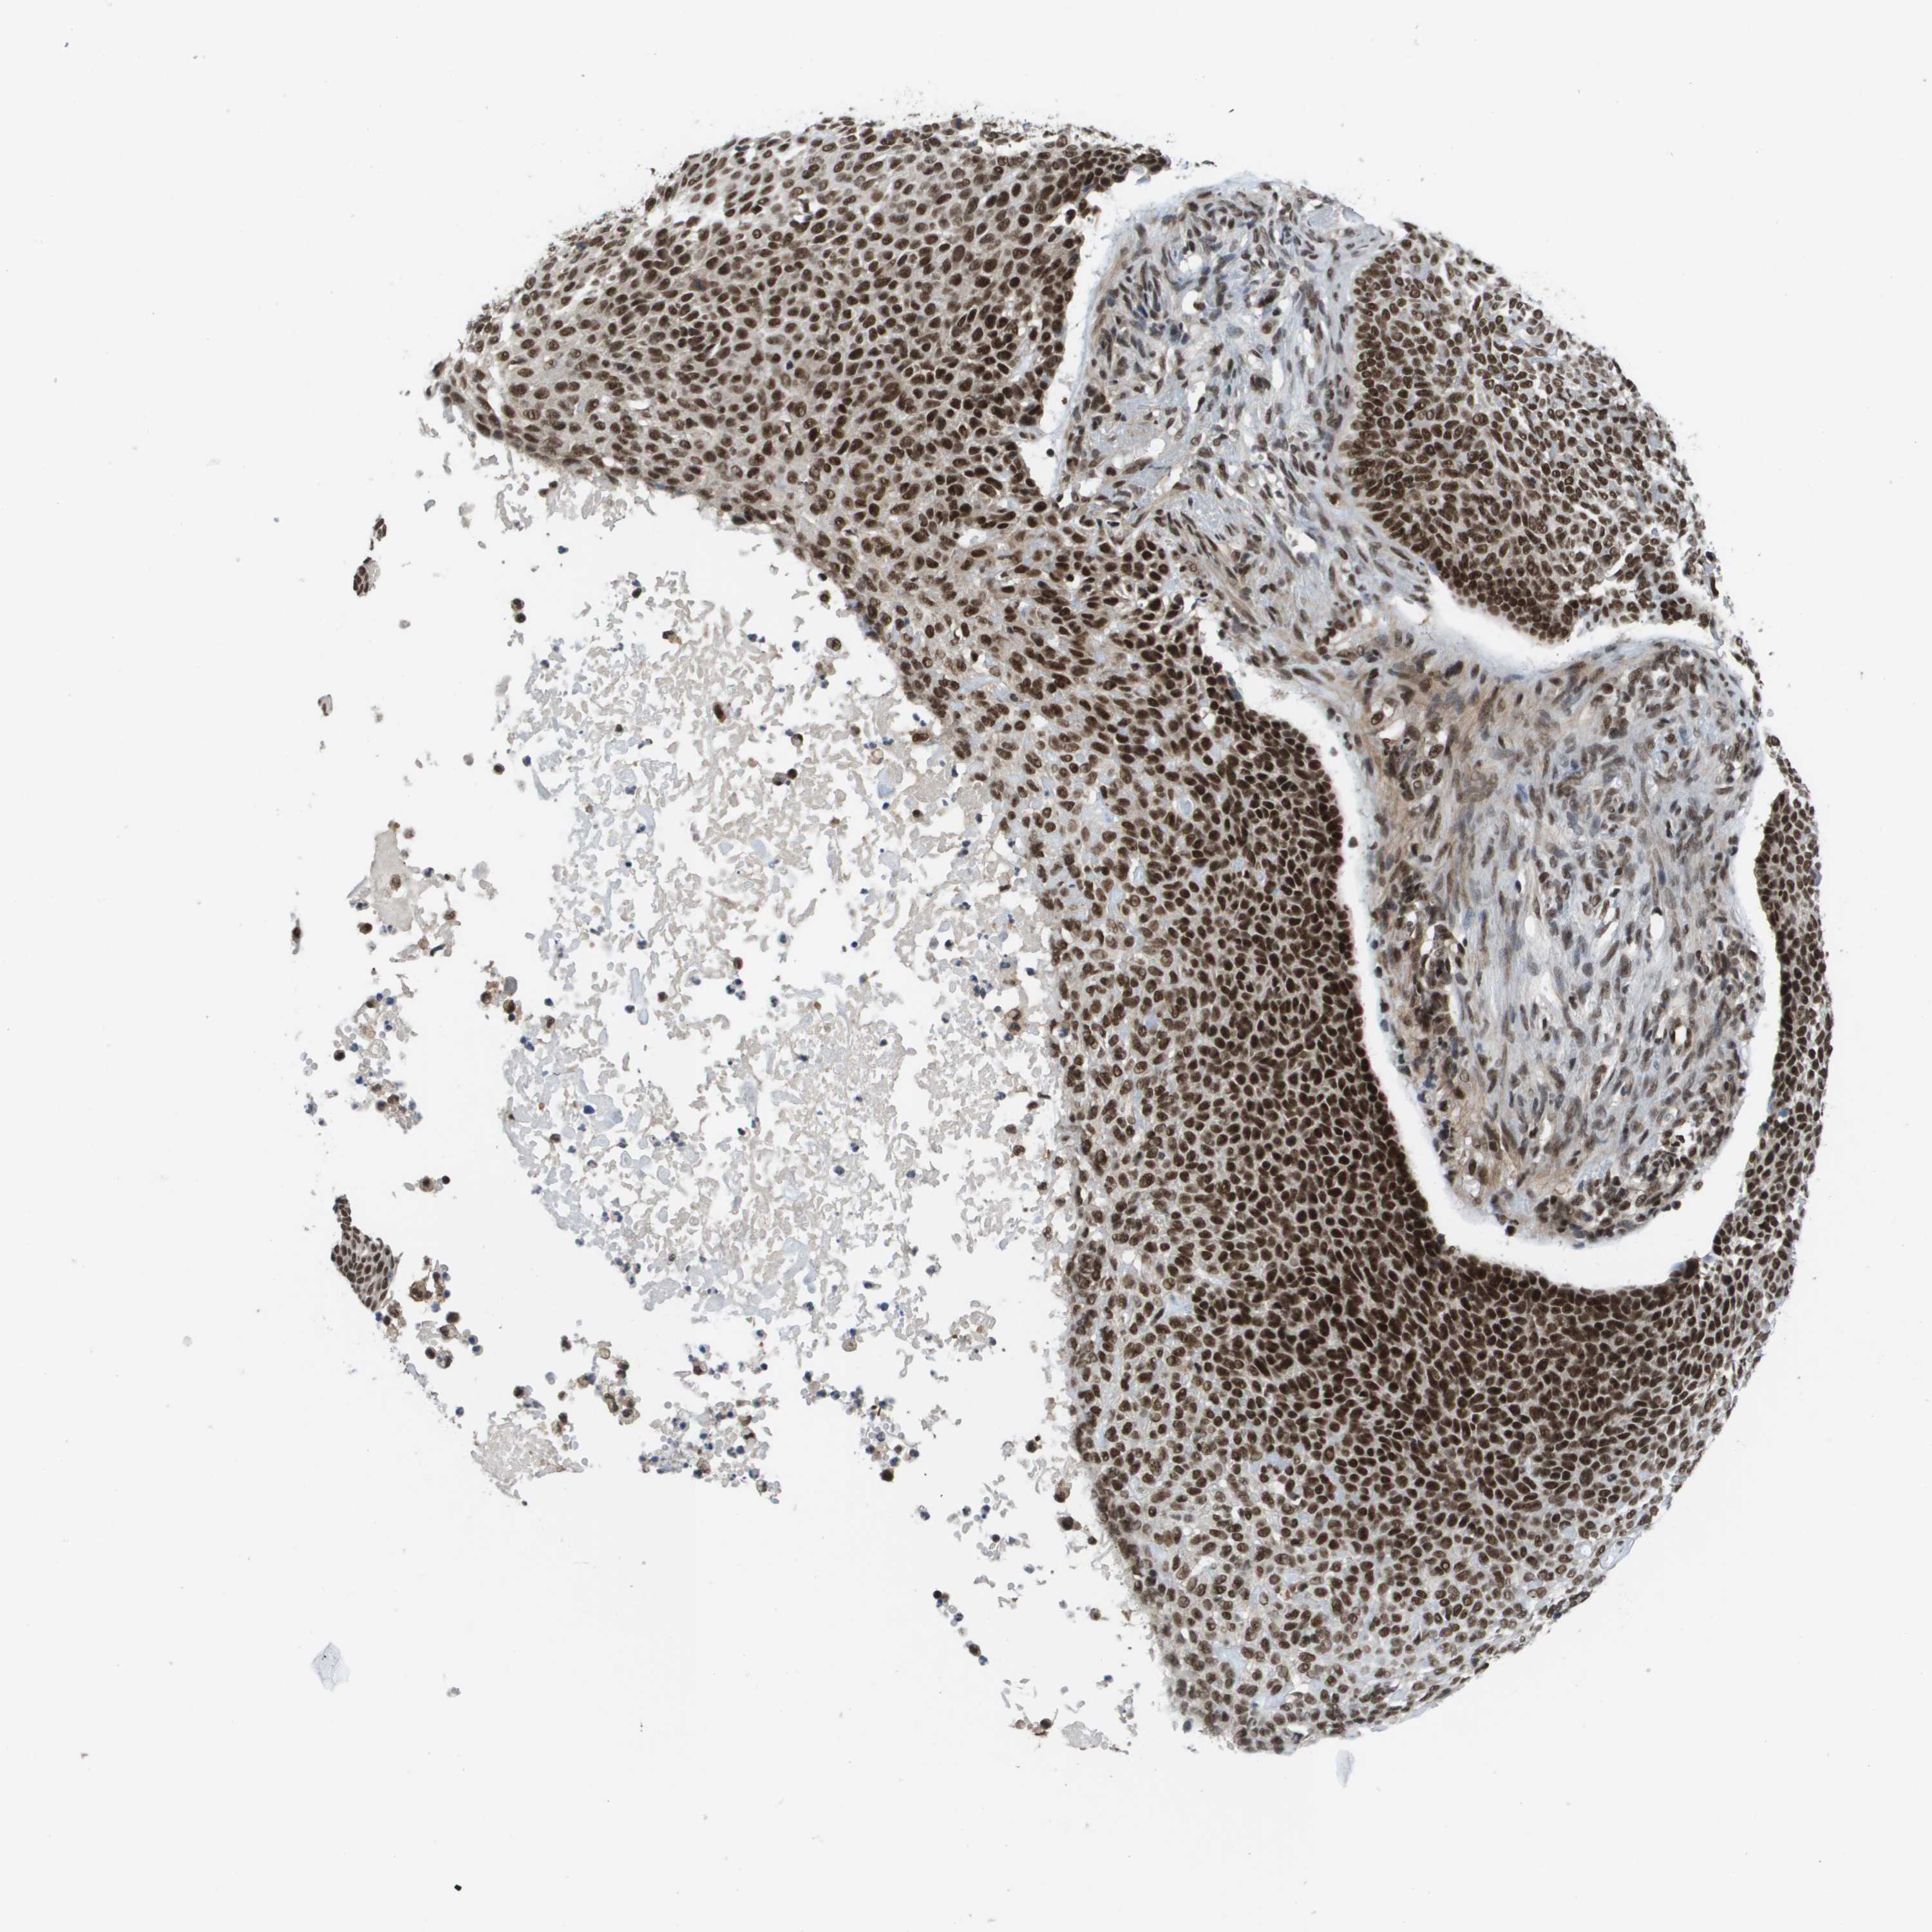

SKIN CANCER - Protein expressioni

A mouse-over function shows sample information and annotation data. Click on an image to view it in a full screen mode. Samples can be filtered based on level of antibody staining by selecting one or several of the following categories: high, medium, low and not detected. The assay and annotation is described here.

Antibody stainingi

Antibody staining in the annotated cell types in the current human tissue is reported as not detected, low, medium, or high, based on conventional immunohistochemistry profiling in selected tissues. This score is based on the combination of the staining intensity and fraction of stained cells.

Each image is clickable and will lead to virtual microscopy that enables deeper exploration of all samples and also displays staining intensity scores, fraction scores and subcellular localization as well as patient and tissue information for each sample.

Antibody HPA019463

Antibody HPA019481

Antibody CAB017151

Staining

High

Medium

Low

Not detected

Intensity

Strong

Moderate

Weak

Negative

Quantity

>75%

75%-25%

<25%

None

Location

Nuclear

Cytoplasmic/membranous

Cytoplasmic/membranous,nuclear

Basal cell carcinoma